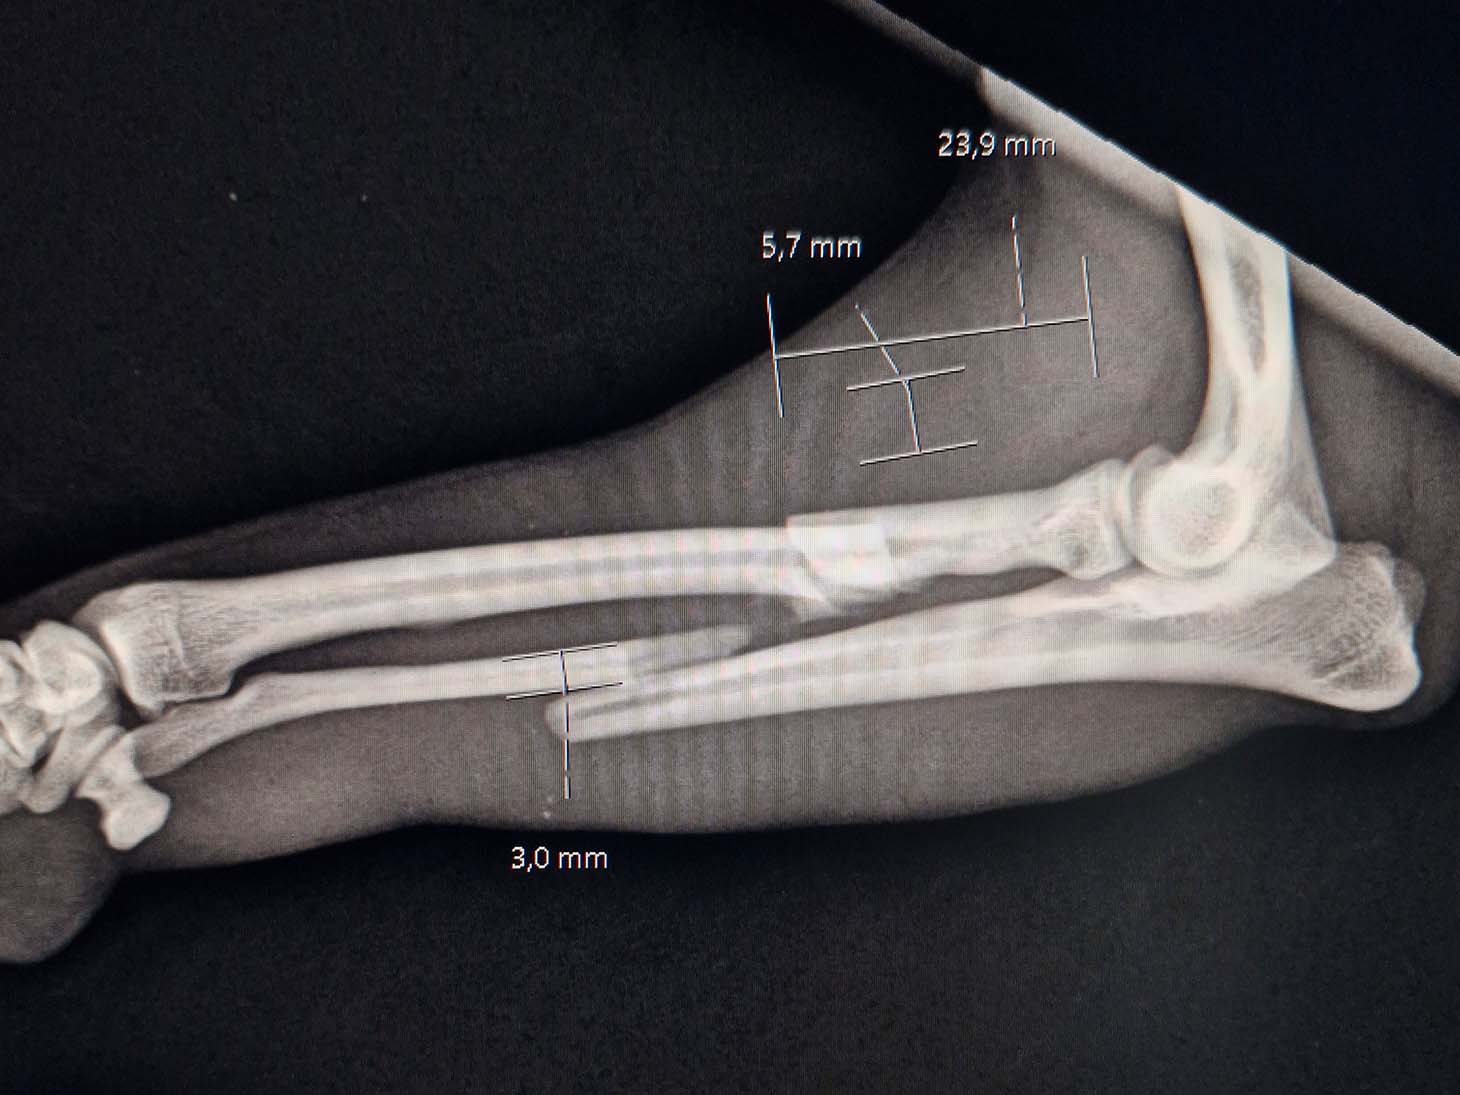

In April 2025, a 3-year-old, 5.6 kg mixed breed dog suffered a severe injury after being struck by a bicycle. The patient presented with a complex proximal comminuted radius fracture and a mid-diaphysis ulnar fracture, classified as an open fracture Grade 1. Thanks to swift surgical intervention and advanced technology, the dog is now back to its energetic self.

- The severely comminuted radius fracture was stabilized using a 2.0 mm titanium LeiLOX plate, specifically chosen to manage the comminution in combination with a supportive repair of the ulna.

- The ulna fracture was addressed with our innovative 1.0 mm titanium LeiLOX plate, secured by 1.3 mm locking screws. This combination provided robust, yet minimally disruptive, fixation crucial for a small patient. The surgical site was thoroughly flushed, and the patient received Cefazolin both perioperatively and for three days post-op to manage the open wound.